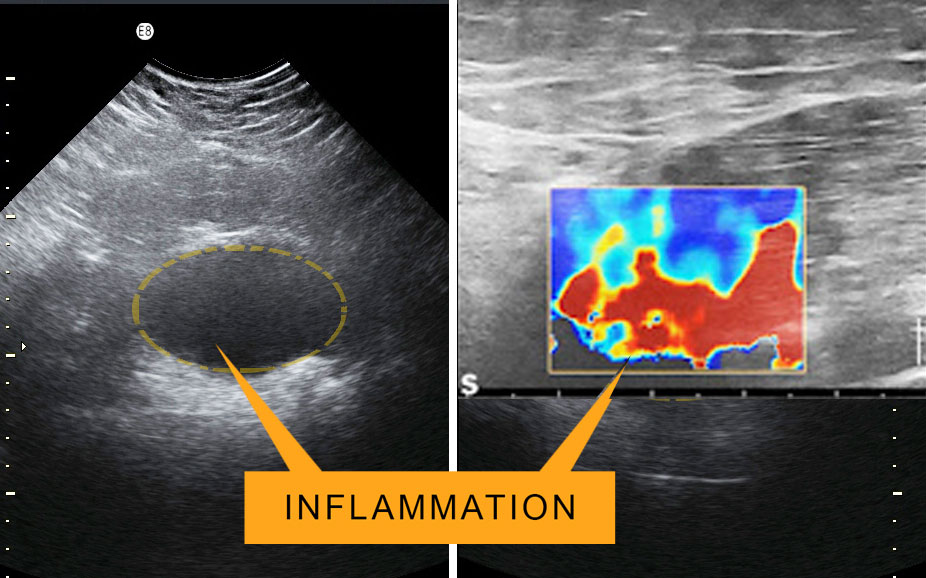

One of the most comprehensive ways to confirm the results of any treatment is by clinically tracking the body's physiological response from underneath the skin. Functional Diagnostic imaging captures measurable data about the injured or inflamed area, allowing both clinicians and patients the ability to identify therapeutic progress in real time. Widely preferred scanning modalities include the Doppler Blood Flow Ultrasound (or sonography) and Elastography, both using high-frequency sound waves to view inside the body. Like an internal video camera, these high speed scanning innovations capture actual movement of the body's internal organs. This offers a vast amount of biometric information about the patient’s condition, in comparison to still images of conventional x-rays. The ultrasound's ability to evaluate abnormalities within the soft tissue in research and clinical trials are widely used in recording evidence-based biomarkers to trace therapeutic efficacy.

DETECTING INFLAMMATION: Part of the complex biological response of body tissues to harmful stimuli (such as pathogens, damaged cells, or irritants) is inflammation. It is also a protective response involving immune cells, blood vessels, and molecular mediators. Detecting the function of inflammation allows us to eliminate the initial cause of cell injury, clear out necrotic cells and tissues damaged from the original insult and the inflammatory process, and initiate tissue repair. The five cardinal signs are heat, pain, redness, swelling, and loss of function. Inflammation is a generic response, and therefore it is considered as a mechanism of innate immunity. Too little inflammation could lead to progressive tissue destruction by the harmful stimulus (e.g. bacteria) and compromise the survival of the organism. In contrast, too much inflammation, in the form of chronic inflammation, is associated with various diseases, such as hay fever, periodontal disease, atherosclerosis, and osteoarthritis.

ACUTE inflammation is the initial response of the body to harmful stimuli from the blood into the injured tissues. A series of biochemical events propagates and matures the inflammatory response within the injured tissue. Prolonged or CHRONIC inflammation, leads to a progressive shift in the type of cells in the inflamed area and is characterized by simultaneous destruction & healing of the tissue from the inflammatory process.

IDENTIFYING TREATMENT EFFICACY: How much effect is your medicine actually having on the body? This level of clinical reporting provides findings on the immediate physiological effects of any therapeutic solution. Results can be based on a BEFORE‐AND‐AFTER visual response comparison, quantifiable biometrics and a sound description of the clinical imaging ‐ thus aiming to show the body's potential reaction to that device (if any) by virtue of a post‐treatment applied scan. Imaging provides scan studies designed to assess, confirm or challenge (if necessary) any device's claims to confirm the device’s impact on the body. Measurable evidence reports can be conducted through the use of advanced ultrasound scans who seek real-time evidence-based valuation.